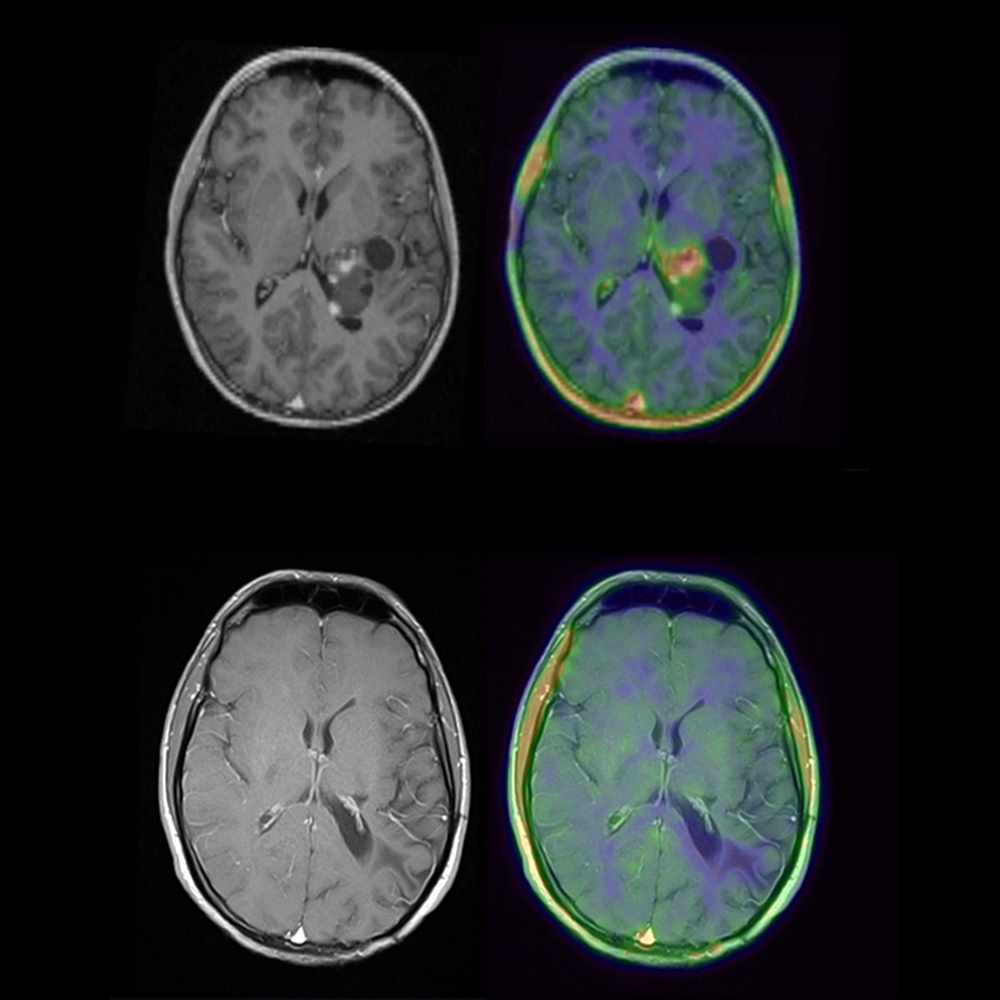

Ergänzung zur Abbildung:

MRT eines Patienten mit Glioblastom vor (oben) und nach (unten) molekularer neuropathologischer Diagnostik und zielgerichteter Therapie. Die Wilhelm Sander-Therapieeinheit NeuroOnkologie ermöglicht neben einer gezielten Diagnostik auch die personalisierte Behandlung von Patienten mit Hirntumoren.